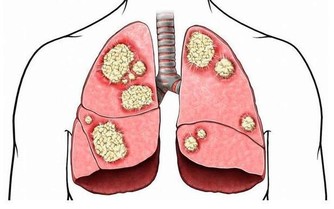

夏天出汗少,感冒、關節炎、失眠就會找上你,高血壓等慢性病的發病率也是成倍漲...

1、排毒防病

出汗是最好的排毒防病方法。研究數據顯示,汗液是體內有害物質的排出途徑之一,在汗液中可以檢測到與尿液中濃度相當的重金屬成分,有時濃度甚至會比尿液更高。

4、提高免疫力

夏天多出汗還有另一個驚人的好處,那就是提高身體免疫力。很多人為了提高免疫力經常會吃一些保健品,一些保健品中所含成分不明,有些保健品含激素,反而抑制免疫系統。

最好的方式就是科學出汗。研究發現,汗液中含有的抗菌肽能有效地抵禦病毒、細菌和真菌;出汗能有效地增強自身免疫力,提高抗菌抗病毒的能力。比如,每天運動30-45分鐘,身體微微出汗,每週5天,長期堅持,免疫力就會增強。

10、預防感冒

出汗實際上有助於抵抗結核病菌和其他危險的病原體。汗液中含有的抗菌肽能有效地抵禦病毒、細菌和真菌;它能進入細菌的細胞膜,對其進行分解。2013年發表在《美國國家科學院院刊》上的研究成果表明:皮離蛋白能夠非常有效地對抗結核病菌和其他細菌。這種天然物質比抗生素更為有效,皮離蛋白這種天然的抗生素在微酸性的汗液中能夠被自然激活。